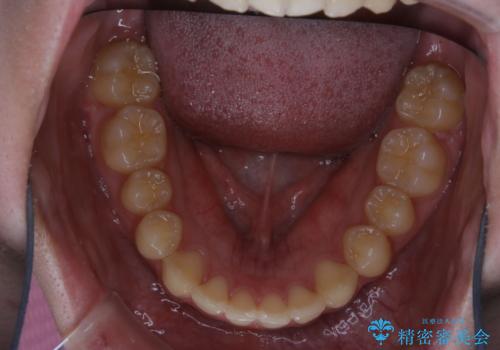

非抜歯で劇的に出っ歯を改善!インビザラインとカリエールの組み合わせ治療

- 治療期間

- 2年

- 患者様、出っ歯のお悩みで来院されました。

骨格の分析を行ったところ上顎も出てはいるのですが、下顎が引っ込んでいる状態であるということがわかりました。

よって上顎の歯を抜いて治療をするのではなく、カリエールという器具を使用して下顎を前に引っ張り出しながら上顎を引っ込めるという治療を行うことにしました。